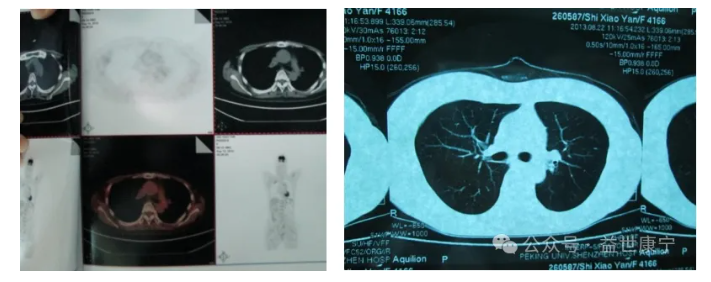

ACTL治疗前影像学图: